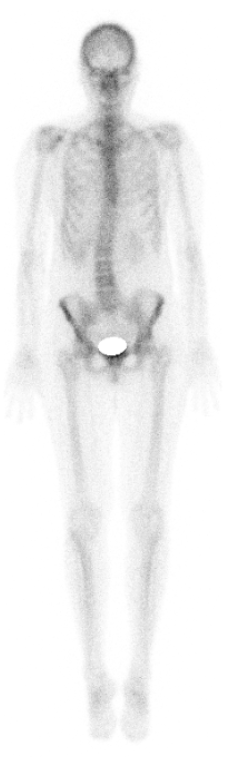

Sonstige Szintigraphien

Auch viele seltenere Untersuchungen werden nach Absprache durchgeführt. Beispielsweise: